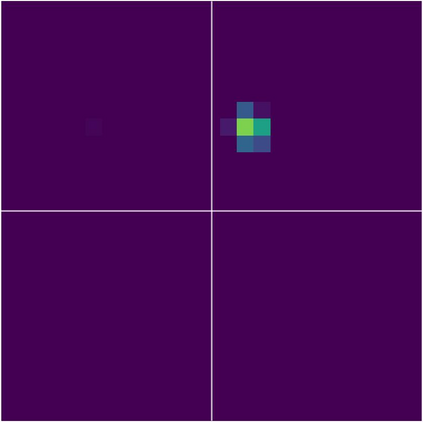

Various imaging modalities allow for time-dependent image reconstructions from measurements where its acquisition also has a time-dependent nature. Magnetic particle imaging (MPI) falls into this class of imaging modalities and it thus also provides a dynamic inverse problem. Without proper consideration of the dynamic behavior, motion artifacts in the reconstruction become an issue. More sophisticated methods need to be developed and applied to the reconstruction of the time-dependent sequences of images. In this context, we investigate the incorporation of motion priors in terms of certain flow-parameter-dependent PDEs in the reconstruction process of time-dependent 3D images in magnetic particle imaging. The present work comprises the method development for a general 3D+time setting for time-dependent linear forward operators, analytical investigation of necessary properties in the MPI forward operator, modeling aspects in dynamic MPI, and extensive numerical experiments on 3D+time imaging including simulated data as well as measurements from a rotation phantom and in-vivo data from a mouse.